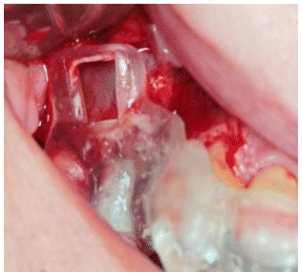

- The guide was placed and checked for correct seating. (Figure 2)

- A piezo surgery motor (Piezomed, W&H, Bürmoos, Austria) was designed to perform the lateral window sinus lift.

- Two C-tech EL 3.8 implants were then placed fully guided and covered with cover screws. (Figure 3)